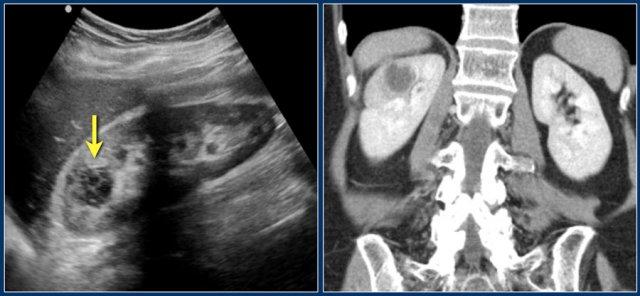

Nghi ngờ khối thận ở thận trái trên siêu âm.

CT cho thấy hình ảnh phồng lồi bờ viền thận trái, thường được gọi là “bướu lạc đà” (dromedary hump).

Giả u (Pseudotumor). Thì thận (Nephrogenic phase) ở bên trái và thì vỏ-tủy (Corticomedullary phase) ở bên phải.

Đây là một trường hợp khác.

Ở thì thận, có thể đặt ra nghi vấn về sự hiện diện của một tổn thương ở thận trái.

Tuy nhiên, ở thì vỏ-tủy, rõ ràng đây là một giả u (pseudotumor).